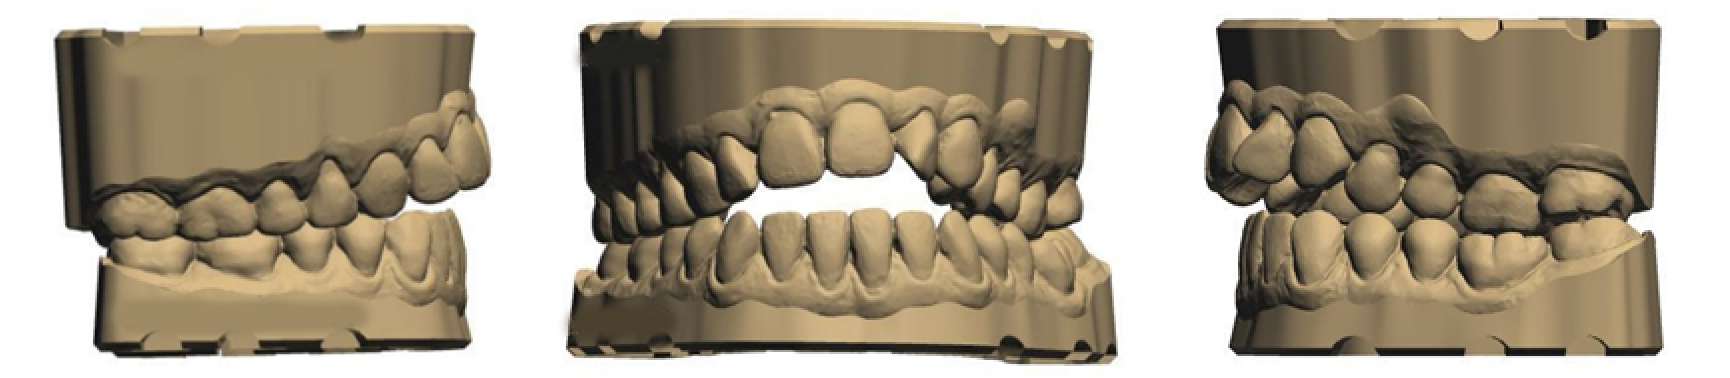

- • Des empreintes (3D)